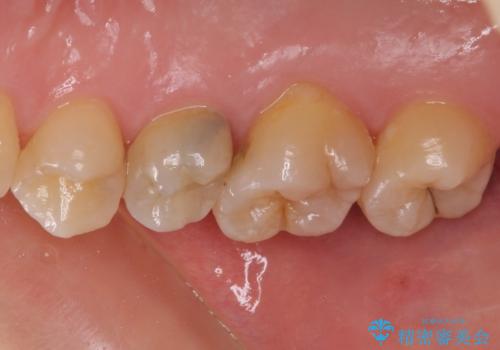

根管治療を行った奥歯は、再発防止や残された歯質を守るため、クラウンによる補綴治療が必要となります。

補綴後6ヶ月経過しレントゲンを撮影したところ、根尖周辺の病変が消失していることが確認できました。